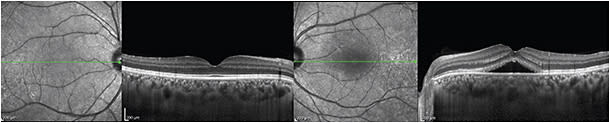

In early AMD, abnormal blood flow, choriocapillaris thinning, and drusen are thought to contribute to thinner than average choroids (115 µm).32 As the disease progresses, the choroidal thickness increases in late AMD and neovascular AMD (239 µm), and then it decreases with the onset of geographic atrophy (Figure 3).33

Figure 3. Macular degeneration. A 78-year-old man presented with gradually decreasing VA in both eyes for five years. Both eyes exhibit geographic atrophy with atrophy of the retina and thinning of the underlying choroid. The thinned retina allows for increased light penetration into the choroid.

A thinner baseline choroid in eyes that developed geographic atrophy was associated with a more rapid progression of disease (1.47 mm2/year) and with worse visual acuity.32 The choroid also appeared thinner in eyes that developed retinal angiomatous proliferation, compared to those with wet AMD.34

Anti-VEGF injections produced little or no reduction in choroidal thickness. A study comparing 20 AMD patients, 20 PCV patients, and 20 myopic CNV patients found choroid thickness remained unchanged following three monthly injections of ranibizumab over 8.4 months of follow up, regardless of etiology.35